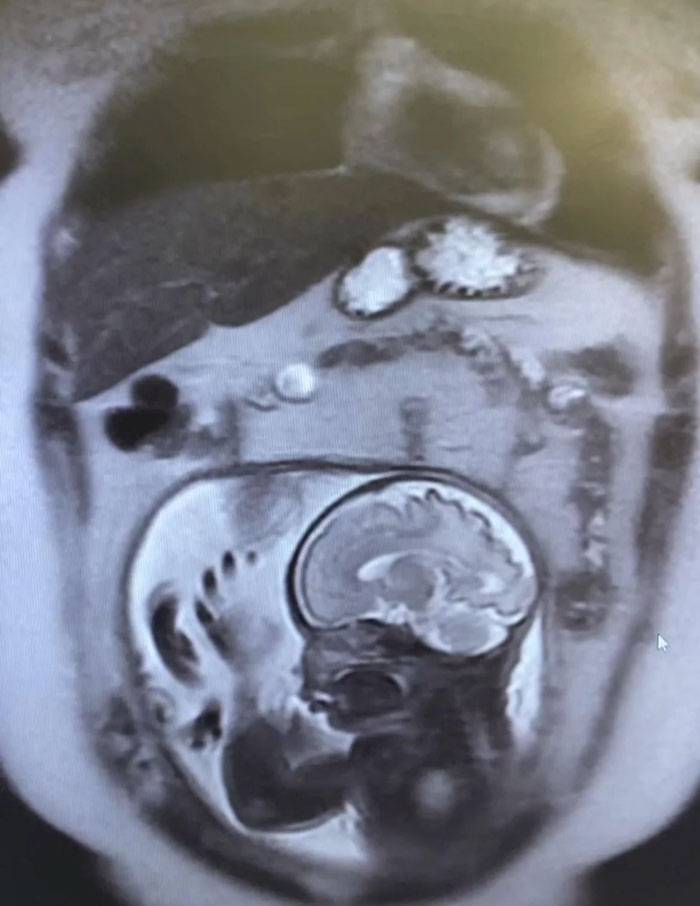

#20 CT Scan Of A 13 Year Old From Gaza

Image credits: AssadShal